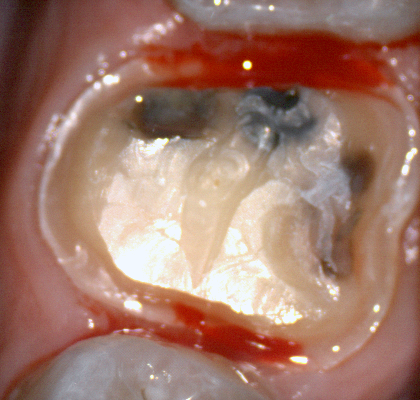

The following pictures depict the sequence of burs we recommend that you use to finish a preparation quickly. While patient is getting numb, take a quick look at the clearance you will need to reach proper material thickness. Once the quadrant is isolated with isolite and optragate, take an occlusal router bur and create a trough to gain the proper depth. Follow that with a flat disk, and you can quickly reduce the occlusal height.

A shoulder bur of .8 mm thickness can help you reduce the interproximal areas as well as the buccal and lingual margin lines. Before finishing the prep, place hemostatic agent like expasyl in the sulcus and place retraction cord. while it is setting, check your reduction. If you need more space, now is the time to reduce some more.